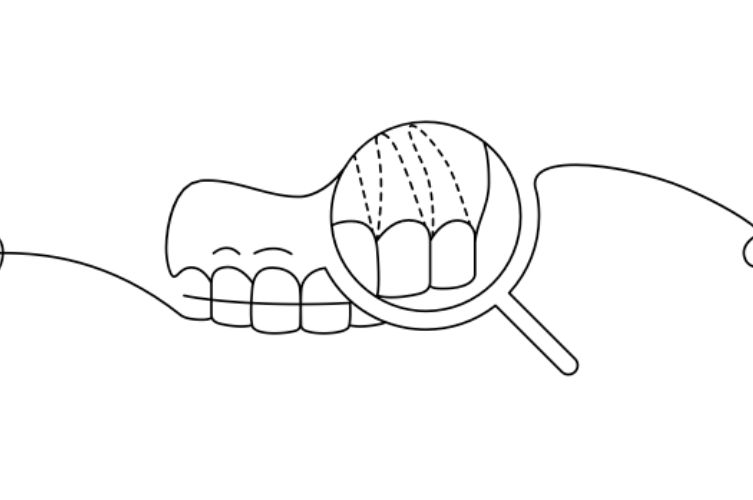

CONTENTION FIXE

Un fil métallique très fin collé sur la face interne des dents antérieures (supérieures et/ou inférieures)

Invisible et confortable, il maintient les dents en position 24 heures sur 24.